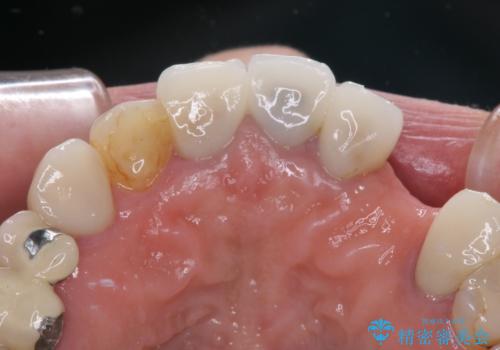

- 他院で矯正治療を終えたものの、むし歯や欠損部の治療が進められないとのことで来院された患者様です。

欠損部や、銀歯やむし歯の大きな歯はセラミッククラウンやブリッジに、小さいむし歯はセラミックインレーにて治療を行うこととしました。